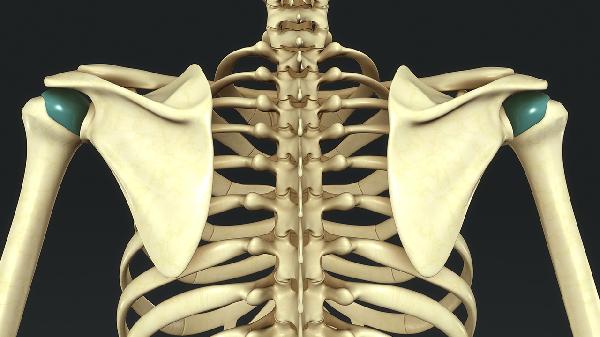

3、肩周炎

祛风骨痛巴布膏对肩周炎引发的肩关节周围肌腱和韧带炎症有缓解效果。肩周炎患者常见肩部活动受限、夜间剧痛和局部压痛。发病可能与劳损、受寒或代谢异常有关。医生可能建议在使用药膏的同时进行康复训练,必要时可配合口服依托考昔片消炎止痛。